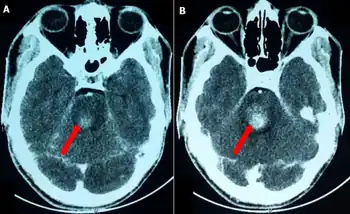

Foville's syndrome is caused by the blockage of the perforating branches of the basilar artery in the region of the brainstem known as the pons.[3] It is most frequently caused by vascular disease or tumors involving the dorsal pons.

Structures affected by the infarct are the dorsal pons(pontine tegmentum) which comprises paramedian pontine reticular formation (PPRF), nuclei of cranial nerves VI and VII, corticospinal tract, medial lemniscus, and the medial longitudinal fasciculus. There is involvement of the fifth to eighth cranial nerves, central sympathetic fibres (Horner syndrome) and horizontal gaze palsy.